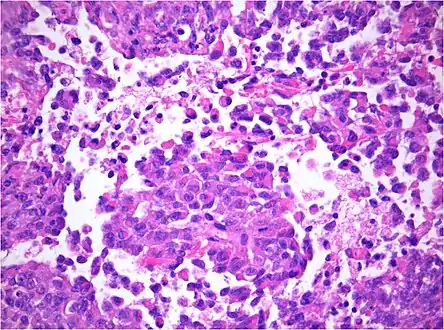

AT/RT and rhabdoid tumor share the term "rhabdoid" because under a microscope, both tumors resemble rhabdomyosarcoma.

Histology

The tumor histopathology is jumbled small and large cells. The tissue of this tumor contains many different types of cells including the rhabdoid cells, large spindled cells, epithelial and mesenchymal cells, and areas resembling primitive neuroectodermal tumor (PNET). As much as 70% of the tumor may be made up of PNET-like cells. Ultrastructure characteristic whorls of intermediate filaments are seen in the rhabdoid tumors (as with rhabdoid tumors in any area of the body). Ho and associates found sickle-shaped embracing cells, previously unreported, in all of 11 cases of AT/RT.[18]

Immunohistochemistry

Immunohistochemistry for INI1, the product of the SMARCB1 gene typically defective in AT/RT: Note the loss of brown staining in the nuclei of tumor cells with defective SMARCB1 as compared to retained staining of nuclei of vascular cells (internal positive control).

Immunohistochemical staining is widely used in the diagnosis and treatment of cancer. Specific molecular markers are characteristic of particular cancer types. Immunohistochemistry is also widely used in basic research to understand the distribution and localization of biomarkers in different parts of a tissue. Proteins found in an ATeratoid/RT are: